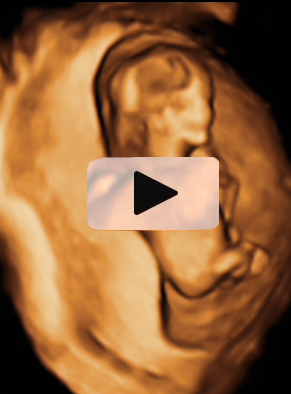

Ecografía Embarazo 2D y 3D Semana 12 - PRUEBAS DIAGNÓSTICAS